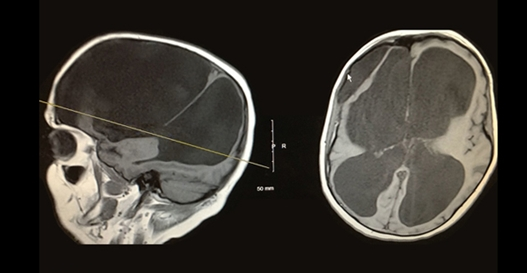

脑积水是通过临床神经病学评估和使用头颅成像技术来诊断的,例如超声波检查法计算机断层摄影,磁共振成像或者压力监测技术。医生根据个人的年龄、临床表现以及已知或怀疑的大脑或脊髓异常的存在来选择合适的诊断工具。